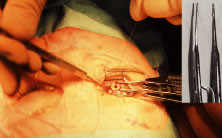

A Stevens' tenotomy hook is passed by the surgeon into the incision and is rotated so that it can be slid underneath the muscle insertion with the tip of the hook held tangential to the globe (Fig. 12). The hook should be passed 2 to 3 mm posterior to the expected location of the muscle insertion. Care is taken not to incorporate intramuscular septum or other adventitial tissue on the hook. When the lateral rectus muscle is secured with the Stevens' or Jameson muscle hook, care should be taken not to bring the inferior oblique muscle up to the insertion (Fig. 13). When the muscle is secured with the Stevens' hook, the hook and the inferior edge of the muscle insertion are elevated and a Jameson muscle hook is passed between the tented muscle tissue and the sclera to secure the muscle at its insertion (Fig. 14). Care is taken to include the entire insertion of the tendon on the hook. The tip of the Jameson hook is gently elevated by depressing the heel of the hook. This maneuver helps to ensure that the entire tendon of the muscle remains captured on the hook. A Stevens' tenotomy hook is placed in the incision, this time anterior to the insertion beneath the conjunctiva (Fig. 15). The Stevens' hook is passed posterior over the orbital surface of the muscle (Fig. 16). Gentle pressure on the Stevens' hook is directed posterior so that the check ligaments and Tenon's tissue that overlie the muscle belly are separated from the muscle capsule with blunt dissection. The hook usually is passed posterior for about 10 mm. When recessing a lateral rectus, attachments between the underside of the lateral rectus and inferior oblique are broken (Fig. 17). Two or three passes over the muscle are made, and, with simultaneous countertraction on the Stevens' hook and the Jameson hook, the conjunctiva is elevated and pulled over the tip of the Jameson hook (Fig. 18A and B).

Fig. 12. The incision is held open with a Manhattan forceps. A Stevens' tenotomy hook is introduced into the incision. The hook is being placed under the rectus muscle without dragging Tenon's tissue and intermuscular septum into the insertion.